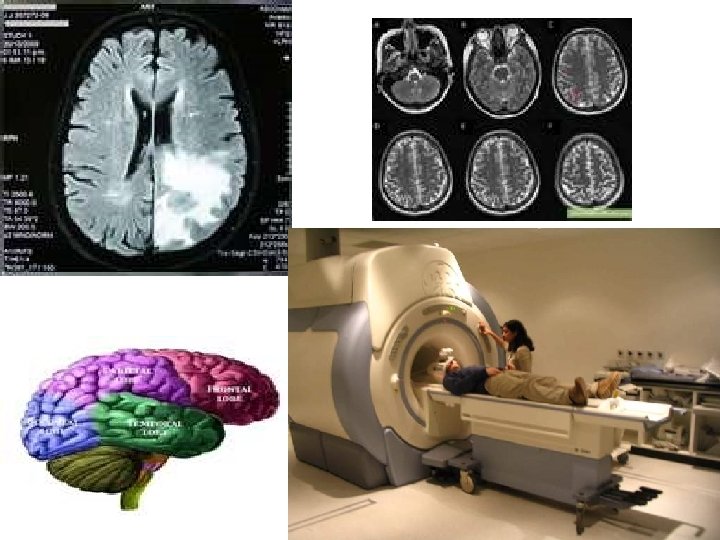

Beyond the optic nerve: Visual field brain imaging: MRI, CTscan

Retina & Optic nerve : Angiography, visual field, OCT, GDX, ERG, EOG, VEP, ultrasonography,